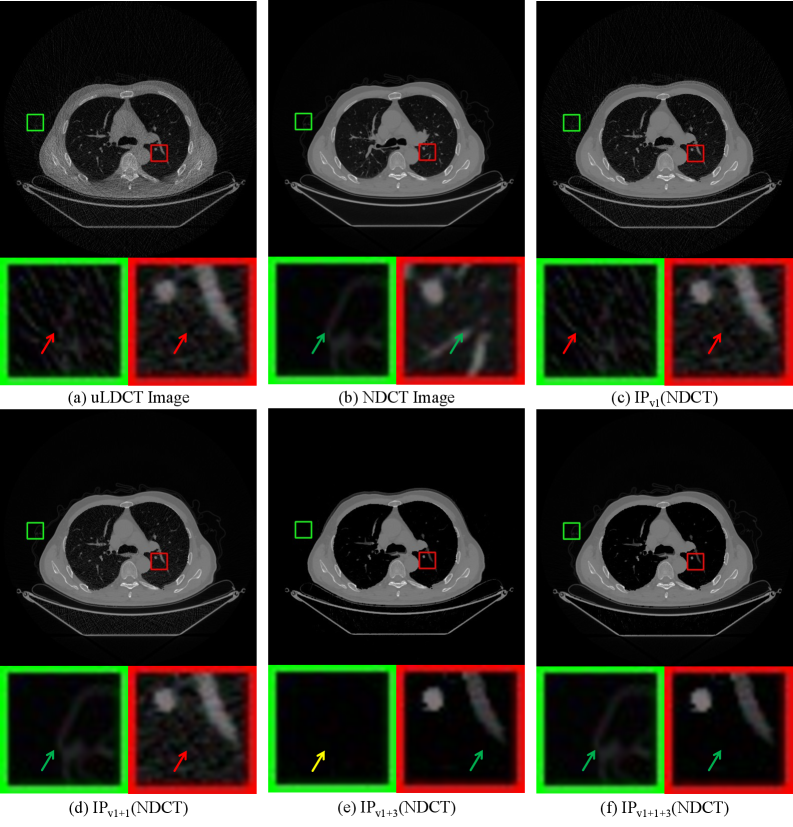

For clarity of presentation, we denote the Remove Background, Add Noise, and Remove Noise modules by the numbers 1, 2, and 3, respectively, as indicated in Figure 2. We conduct ablation studies by incorporating Module 1 and Module 3, individually and in combination, into the IPv1 baseline. We then compare the distribution distance between the resulting processed images (IPv2(NDCT)) and the original NDCT. The experimental results, shown in Table 2, indicate that, compared to IPv1, integrating either Module 1 or Module 3 alone brings the processed images closer to the NDCT distribution. Adding both modules simultaneously further enhances the strategy’s capability. Figure 4 provides an intuitive illustration of the underlying mechanism. Using Module 1 alone effectively denoises the background but fails to denoise the lung tissue regions. Conversely, using Module 3 alone denoises the lung tissue but may remove important information from the background. The combination of Module 1 and Module 3 leverages the strengths of both, achieving effective denoising in both the background and lung tissue areas.

Refer to caption

Figure 4: Visualization of processed NDCT results generated by different modules within the purification strategy, which serve as labels during testing. (c) Result from the previous purification strategy (IPv1). (d) to (f) Results from adding Module 1, adding Module 3, and adding both Module 1 and Module 3 to IPv1, respectively. Red arrows indicate the presence of noise, green arrows indicate the absence of noise, and yellow arrows indicate the removal of useful information.